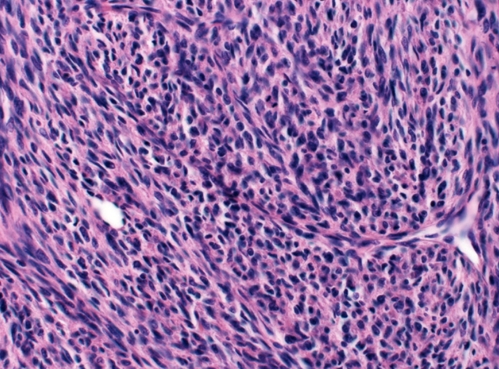

Granulosa Tumor

The granulosa cells are small and cuboidal in shape, grow in cords or sheets, and form follicle- or rosette-like structures (Call-Exner bodies) that have a gland-like appearance with a pink eosinophilic center and coffee bean nuclei (black arrows). Theca cells are plump with lipid contents, which give the mass a yellow color on gross inspection.